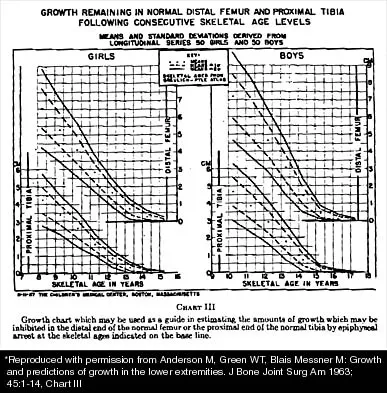

Question 49

A 10-year-old girl with a monoarticular pattern of juvenile rheumatoid arthritis (JRA) has had a 3-cm limb-length discrepancy since age 8 years when inflammation in the right knee came under good medical control. Because her right leg is longer, the patient states that she would like her legs to be close to equal in length in the future. A growth-remaining chart is shown in Figure 14. Management should consist of

Explanation